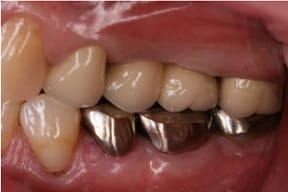

CASE03 臼歯部インプラント ~ブリッジがグラつき始めている~

- セラミック冠

ブリッジの部分の下顎の骨が吸収をおこし、ブリッジで支えている歯がぐらつき始めている状態。予後を考えた結果、ブリッジで支えることが困難という診断のもと、インプラント治療を施したケースです。